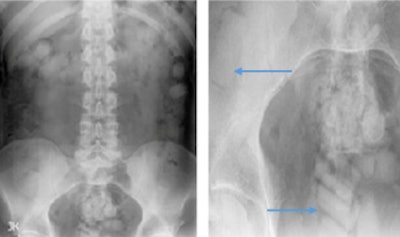

The authors have also encountered cases of colonic packing. They have seen smooth, well-defined radiopaque densities -- sometimes variable in size and shape -- scattered throughout the bowel lumen. The characteristic 'double condom' sign may be visible, and the complications can include bowel obstruction or perforation.